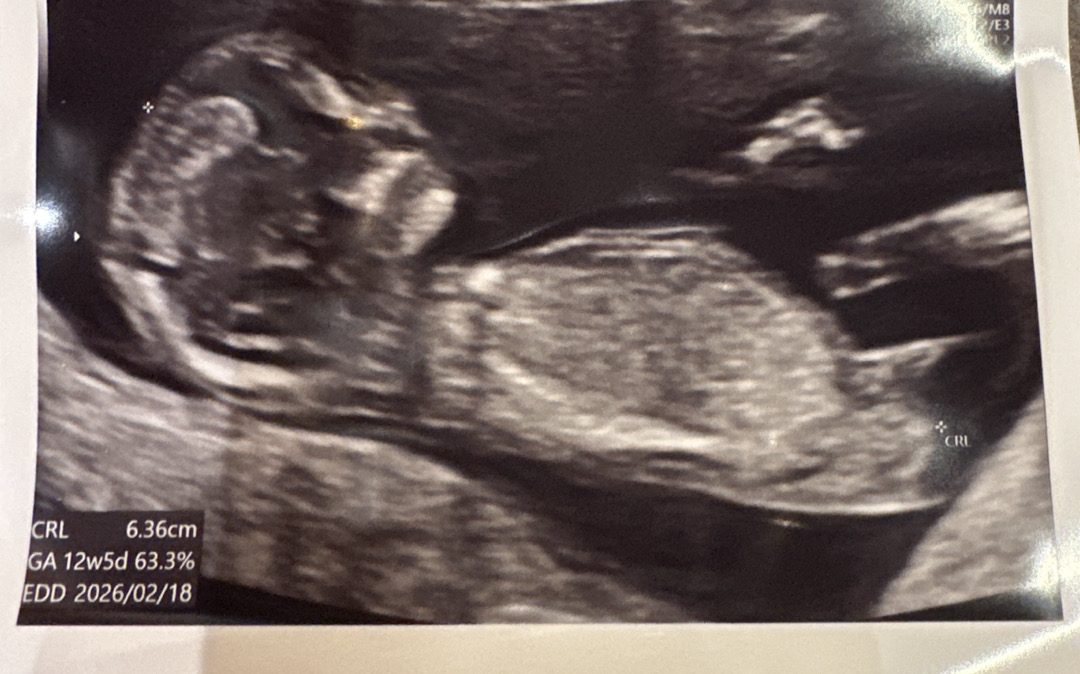

12주차 각도법 알려주세요~~

성별 너무 궁금하네요 ㅎㅎㅎ 각도법 아시면 알려주세요~